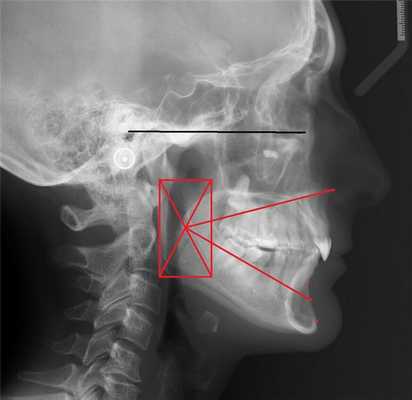

Используя ТРГ боковую мы предположили параметры будущих зубов

- обращаем внимание на вестибулярную позицию вторых резцов, то есть наклон зубов вперед

- мы видим избыточный наклон центральных резцов назад - это приводит к уменьшению “функционального пространства “ и, соответственно, зубы нижней челюсти пытаясь избежать контакта с зубами верх. Челюсти заставляют мышцы смещать нижнюю челюсть назад, что сразу увеличивает давление головки нижний челюсти на структуры ВНЧС

Итак, на сканах мы в полном объёме смогли оценить повреждения зубных рядов и сделать первые предположения о причине возникновения дисфункции ВНЧС. Для более чёткого понимания нарушений биомеханики сустава мы провели аксиографию (исследования движений сустава) на котором мы подтвердили что нижняя челюсть занимает не самое идеальное положение и траектория движения имеет отклонения, связанные с попыткой нижней челюсти обойти препятствие ( зубы верхней челюсти ) .